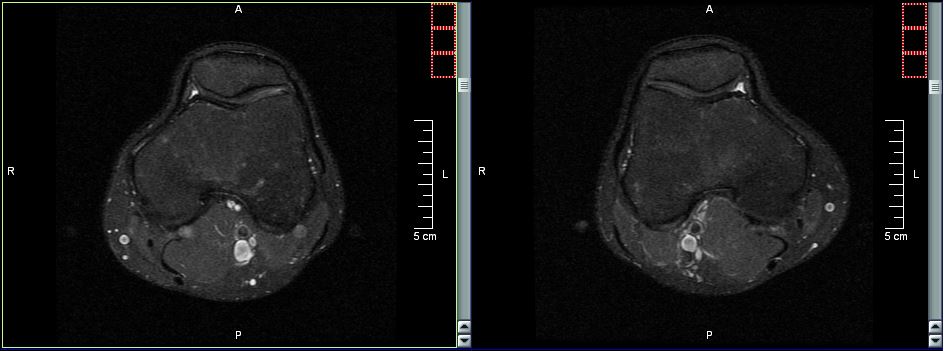

Dalle tue parole sembra che ti sia stata riscontrata una condropatia o sindrome femoro.rotulea, cioè una sofferenza cartilaginea nell'articolazione tra la faccia interna della rotula ed i condili femorali.

Sempre dalle tue parole sembra che la causa POTREBBE essere un disallineamento rotuleo (dico "potrebbe" perchè non si possono escludere a priori la coesistenza di concause...come una modalità esecutiva non corretta di alcuni movimenti, oppure una extrarotazione del piede, o un "crollo della volta plantare" con conseguente iperpronazione del piede, ecc.ecc.). Il disallineamento della rotula c'è, io ad occhio nudo non la vedo, ma fermo e in posizione eretta l'ortopeda l'ha visto.

La falda fluida rilevata, immagino, con una ecografia fa pensare ad un conseguente fenomeno infiammatorio. Esatto, proprio tramite ecografia è stato rilevato questo leggero versamento e diagnosticata l'infiammazione.